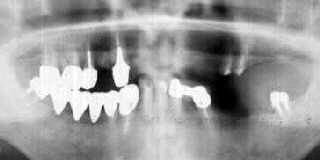

初診時 パノラマ 10年後 パノラマ

65歳 男性

インプラントの動揺に伴う脱離→二次カリエス発生

下顎前歯部の骨吸収は1/2以上であったが、それ以外の部位は年齢の割に歯槽骨吸収が 軽度であった。決して良好な清掃状態ではなかったが、歯牙保存に対する意欲は強いように 思われた。

処置および経過:

歯を植えることよりも、現在の歯を大切にすることを説明してから治療開始。 歯周初期治療と伴に、上顎のカリエス治療を行ったのち、下顎の残存歯に対して歯周外科 処置をおこなった。下顎は、連結冠と義歯による機能回復を計りメインテナンスに移行したが、 義歯に対する不満とインプラントへの願望が強くやむなくインプラントを行うことになった。 右下の7番部位に他家移植を施行し、左右の6・6番部位にインプラント(バイオセラム)を 植立してフルブリッジによる機能回復を計画し、実行した。  治療終了後4年間くらいはメインテナンスを継続していたが、次第に足が遠のきその後2年 に一度程度来院するにとどまったまま10年が経過した。「34部の歯肉腫脹の訴えに対して レントゲン診査を行った結果、補綴物脱離による二次カリエスが確認された。放置しておくと 支台歯が破壊されてしまうと判断しBridgeの除去を決断した。 Bridgeの除去に伴い動揺するインプラントは撤去して、新しいインプラントを植えることとした。

考察:

インプラントの除去に際して、比較的骨植が堅固だったのをみて“勿体無い”気持ちになりました。 もっとも、骨植堅固な支台歯が脱離したのはインプラントの動揺が原因で、インプラントに動揺が なければもっと永く機能したものと思われる。 本性例は、バイオセラム(京セラ)を使った最後の症例で、当時のインプラントの限界は十分熟知 していた反面、フルブリッジにすれば長期間安定することに大きく依存した症例です。